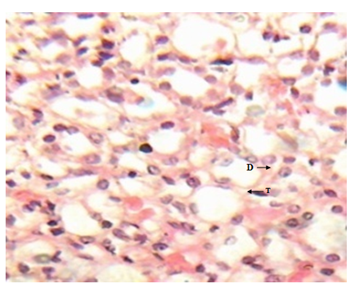

The results of this study are in accordance with those of Datta et al.;38 Jackson et al.;39 Sait & Hattice.40 Enas.23 reported an increase in antioxidant capacity in alloxan treated rats which he attributed to over expression of antioxidant enzymes in response to glucose-induced oxidative stress. Serum GGT concentration was higher whereas TAC concentration was lower in diabetic rats compared to the normal control. This negative correlation between GGT and TAC could be attributed to oxidative stress in diabetes which depletes the antioxidant defense system resulting in a compensatory increase in GGT. Chronic hyperglycaemia and dyslipidaemia are associated with a variety of metabolic disorders in human and animal diabetes Handen et al.41 causing oxidative stress, depleting the activity of the antioxidant defense system and resulting in elevated levels of ROS Dahech & Handen et al.42,43 The inverse association between antioxidants and serum GGT has indicated the possibility that serum GGT might be associated with oxidative stress Lee et al.;44 Takigawa et al.45 In the present study, HbA1c was used as a marker of glycaemic control. The significant increase in HbA1c concentration in the diabetic rats when compared to the control may be attributed to the persistent hyperglycaemia. Persistent hyperglycaemia, uncontrolled or poorly controlled diabetes results to an increased glycosylation of a number of proteins including haemoglobin because the excess glucose in blood reacts with haemoglobin. This result supports the work done by Aruna et al.;46 Muthulingam.;47 Neeraj et al.;48 Vallejo et al.49 on higher HbA1c levels in diabetic rats. Our study also showed that alloxan-induced diabetes in rats produced alterations in the hepatic structures as well as functions while the control group showed no pathological changes. This was evident from the histological sections which showed mild and moderate periportal lymphocytic infiltrations with sinusoidal dilatations as well as serum elevation of transaminases activities (ALT and AST) which are indices of liver cell damage. These changes could be attributed to the altered architecture of the hepatocytes, and these subtle membrane changes are sufficient to allow the leakage or passage of intracellular enzymes into blood, hence their increased concentrations in serum. Moreover, cell damage increases permeability causing cytosolic isoenzymes to spill into the interstitium, and from there into the peripheral blood. The pathological changes in liver of alloxan and streptozotocin induced diabetic animals have been previously reported Herrman & Sandhu et al.50,51 Zhang et al.52 reported an increased serum levels of ALT and AST in diabetic rats. Ohaeri,53 Al-shamshi et al.;54 Fadillioglu et al.55 also reported an increased serum ALT and AST in diabetes patients than in the general population (Figures 1-4).

Figure 1 Liver micrograph of control rat showing at 3 and 5 weeks. (H & E stain X400).

Figure 1 Liver micrograph of diabetic rat showing mild periportal lymphocytic infiltration(P) and hepatocyte disorientation (H) at 3 weeks.(H & E stain X400).